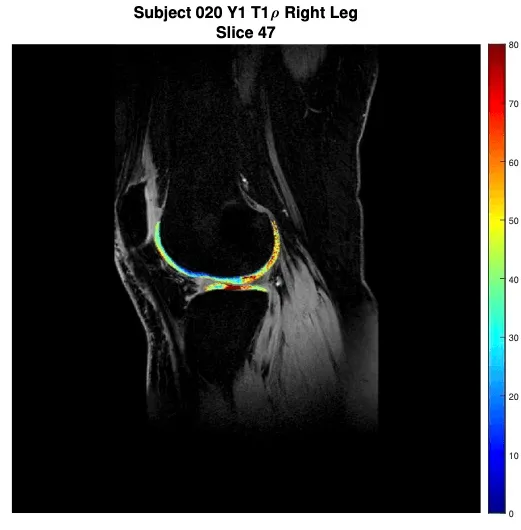

Below are image examples from several types of MRI equipment that researchers may use.

Orthopedic Images

Dr Beynnon - PTOA study